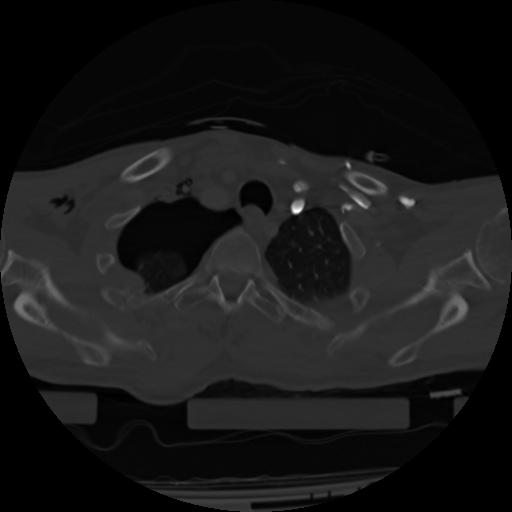

21 ANGIO,CE,Axial,3.0,ANGIO,,